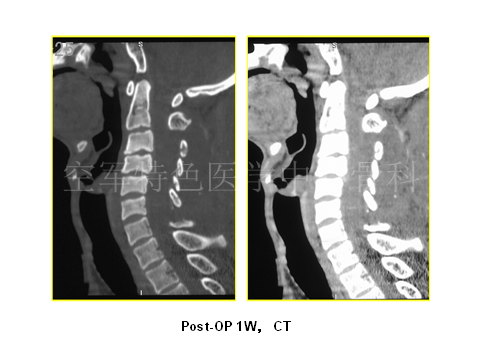

最终陈医生采取的治疗方案与各位专家不谋而合,患者最终行颈后路C3-6椎管扩大成型术,术后患者自觉症状明显减轻,JOA评分:12分。术后3年随访,患者步态稳健,无明显不适。

随访影像学如下: